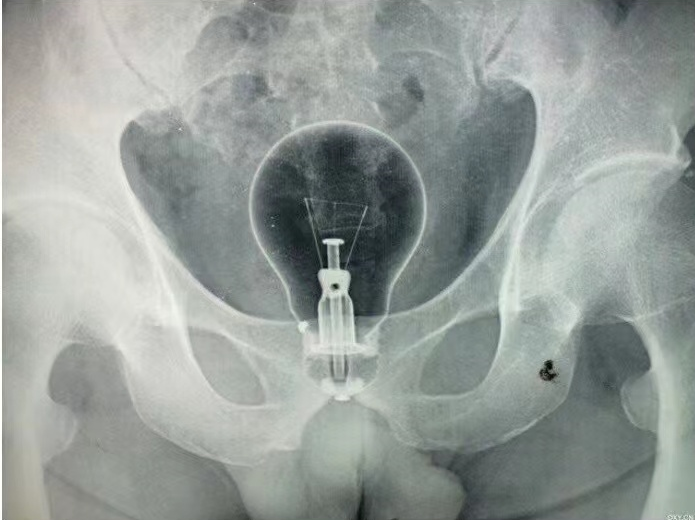

叶医生见过听过的肛门异物也是种类繁多,他告诉记者,最多的是各种水果和蔬菜,还有奇形怪状的比如灯泡、洗发水罐子等,小龙虾、黄鳝等他也有所耳闻。

“比如取灯泡的情况,因为灯泡是玻璃制品,取出时要保证其完整性,否则玻璃碎裂后损伤直肠壁,很容易造成肠穿孔,病人极有可能需要做肠切除和造口。”叶医生还提醒,即便顺利取出肛门异物,患者也有可能面临因为剧烈扩肛后导致的括约肌损伤,括约肌损伤后,会导致患者肛门失禁,十分痛苦。“这对于患者的生理和心理都是极大的打击,所以千万不要因为一时的猎奇心态,就挑战自己的身体极限。”叶医生语重心长地呼吁:别再往这里塞东西了......